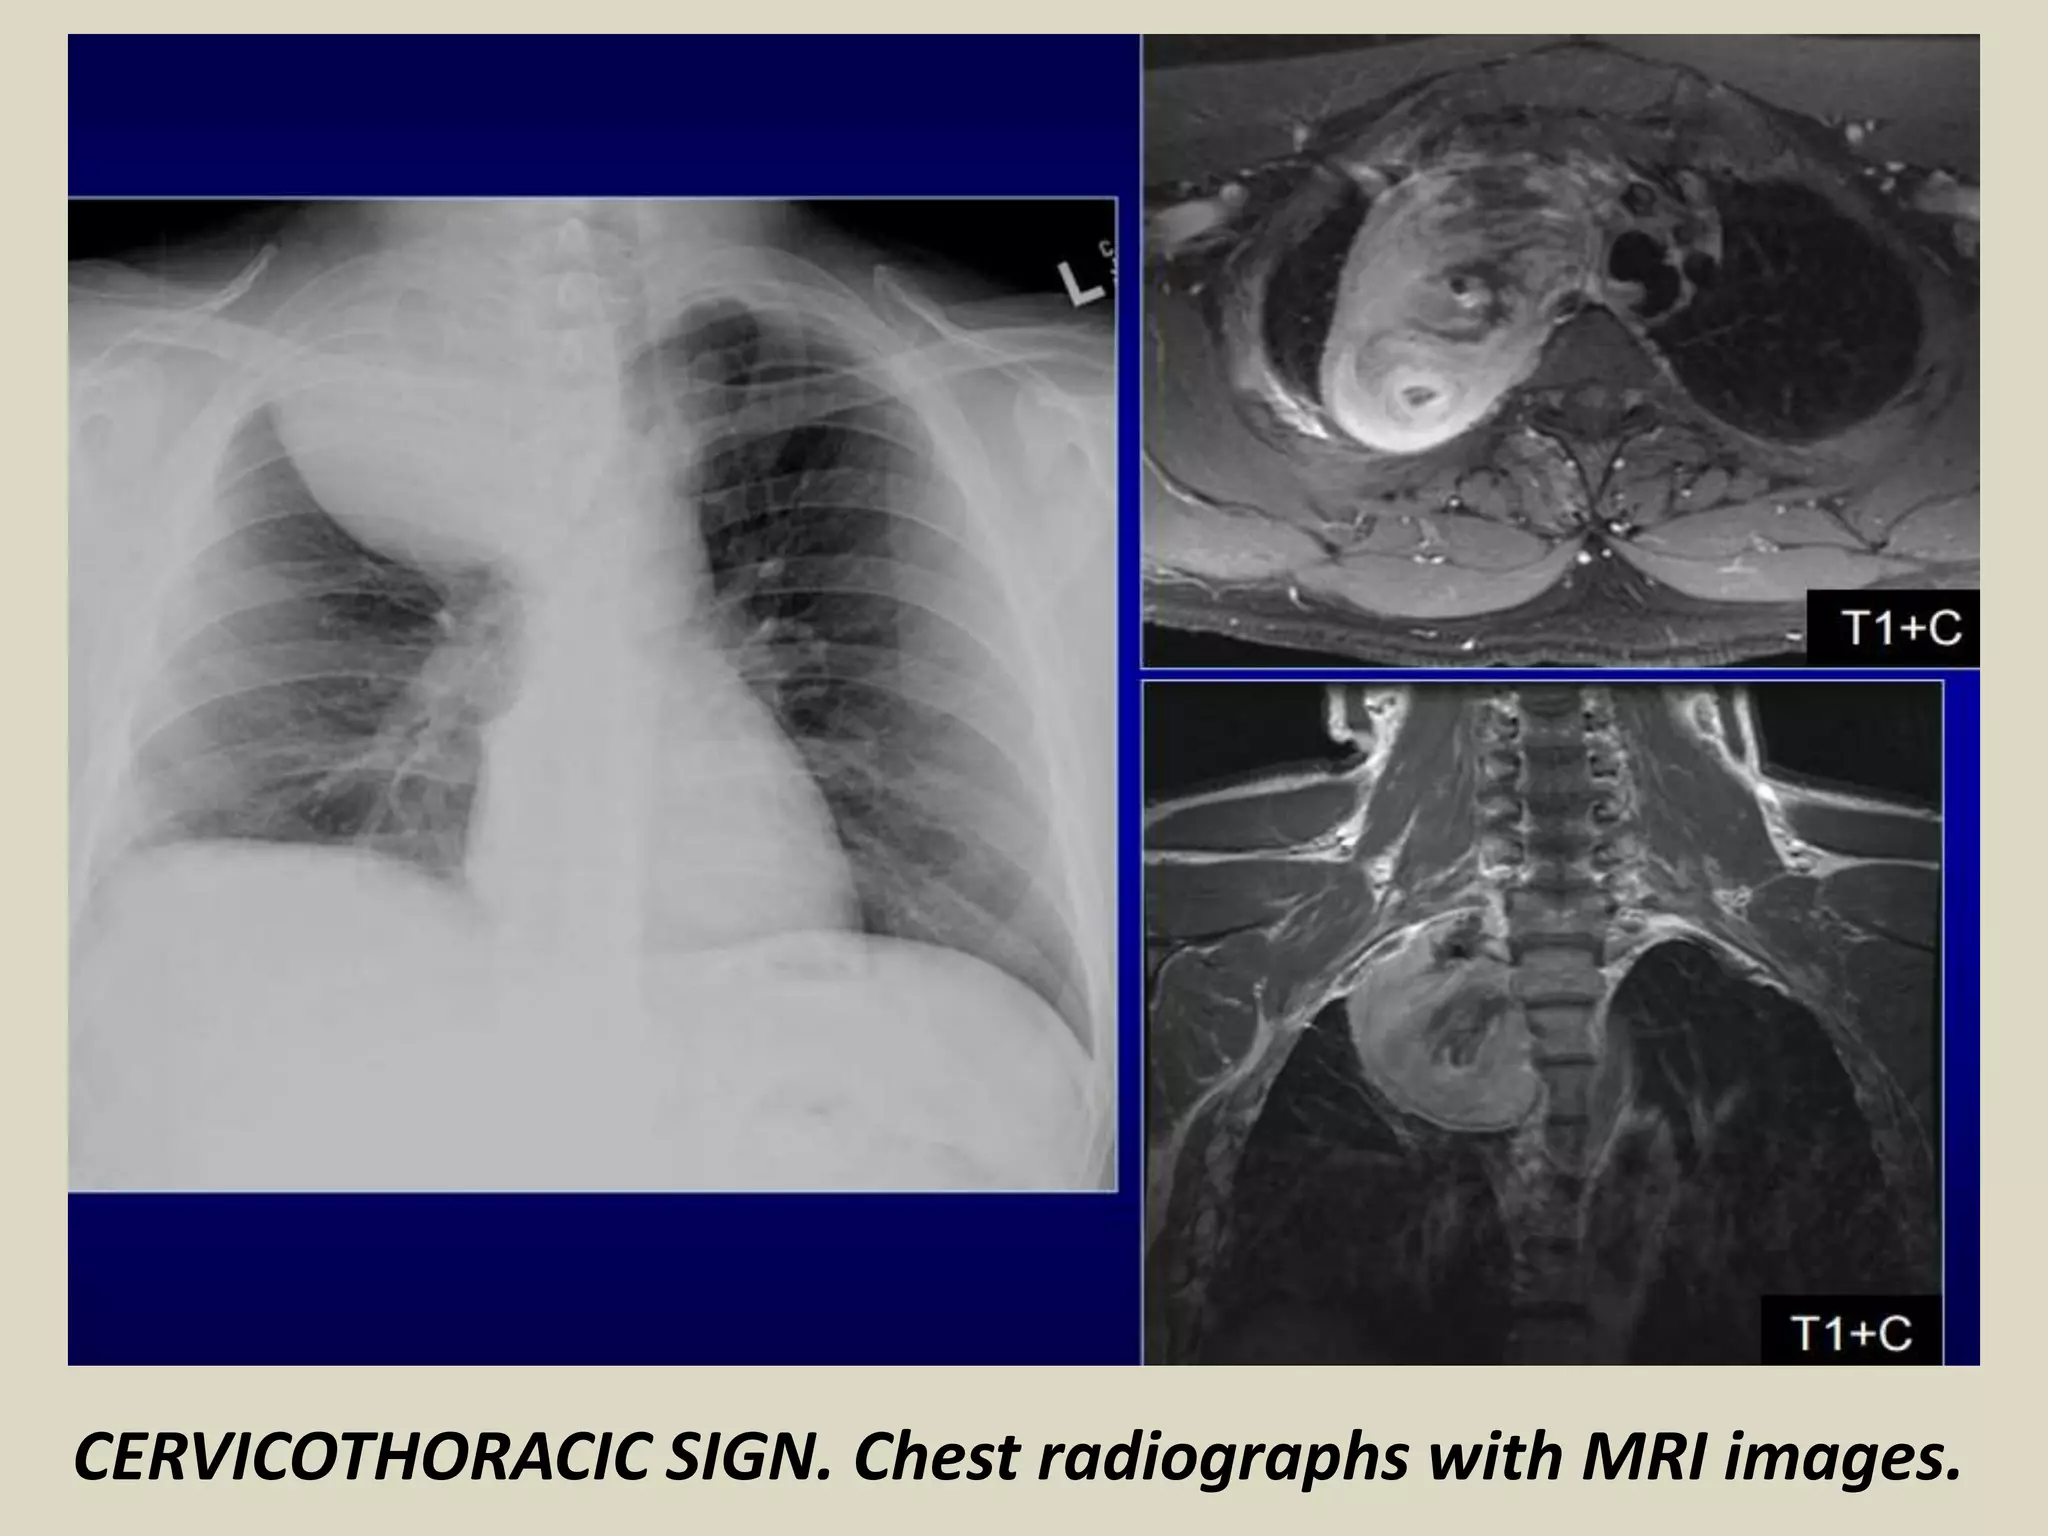

CERVICOTHORACIC SIGN

Used to determine location of mediastinal lesion in the upper

chest

Based on principle that an intrathoracic lesion in direct contact

with soft tissues of the neck will not be outlined by air

Uppermost border of the anterior mediastinum ends at level

of clavicles, so when the cephalic border of a mass is obscured

at or below the level of the clavicles, it is deemed to be a

“cervicothoracic lesion” involving the anterior mediastinum

Middle and posterior mediastinum extends above the clavicles

Mediastinal mass projected superior the level of clavicles must

be located either within middle or posterior mediastinum

More cephalad the mass extends the most posterior the

location

CERVICOTHORACIC SIGN. Chest radiographs with schematic drawings. Lymphoma.

CERVICOTHORACIC SIGN. Chest radiographs with MRI images.

CERVICOTHORACIC SIGN Used todetermine location of mediastinal lesion in the upper chest Based on principle that an intrathoracic lesion in direct contact with soft tissues of the neck will not be outlined by air Uppermost border of the anterior mediastinum ends at level of clavicles, so when the cephalic border of a mass is obscured at or below the level of the clavicles, it is deemed to be a “cervicothoracic lesion” involving the anterior mediastinum Middle and posterior mediastinum extends above the clavicles Mediastinal mass projected superior the level of clavicles must be located either within middle or posterior mediastinum More cephalad the mass extends the most posterior the location

• 65.

CERVICOTHORACIC SIGN. Chestradiographs with schematic drawings. Lymphoma.

• 66.

CERVICOTHORACIC SIGN. Chestradiographs with MRI images.